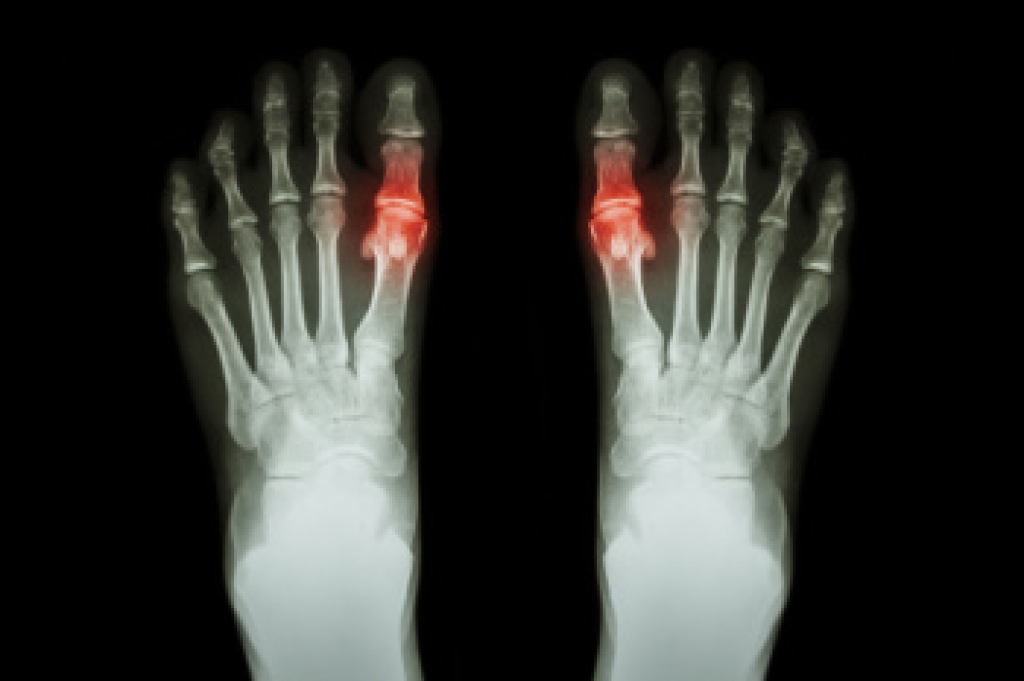

Swollen feet can also be caused by bone and tendon conditions, including fractures, arthritis, and tendinitis. Additionally, there may be skin and toenail conditions and an infection may cause the feet to swell. Patients who take medicine to treat high blood pressure may be prone to getting swollen feet.